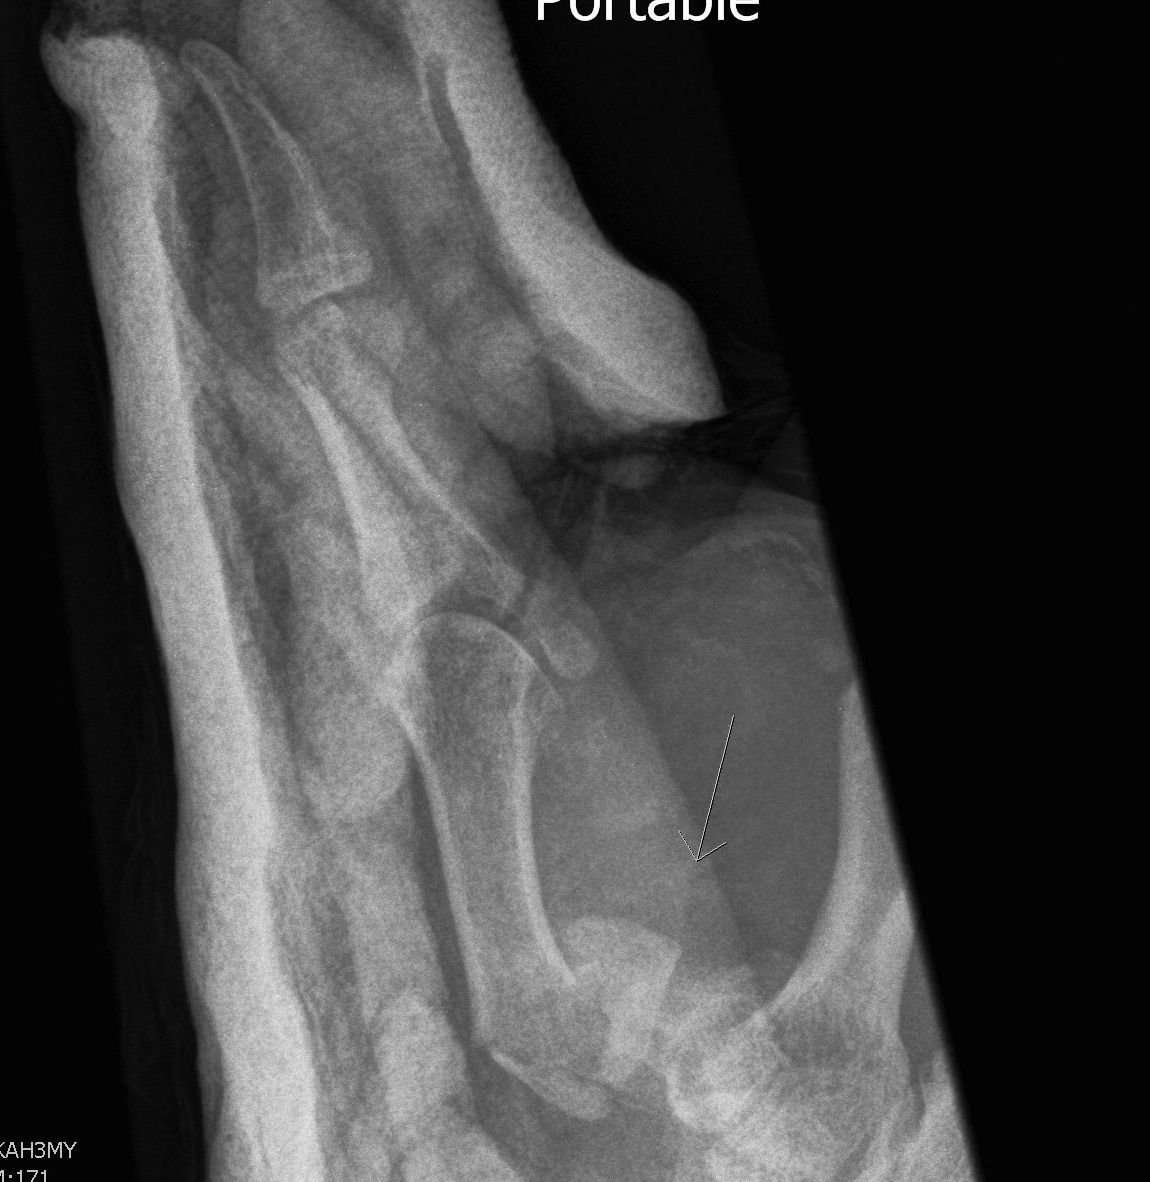

A. Bennett's Fracture

Fracture

- oblique intra-articular fracture

- small volar fragment remains in situ as attached to beak ligament

- metacarpal displaces proximally and dorsally due to APL

- inherently unstable